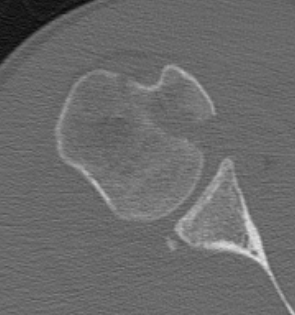

CT

LTLT

Lesser tuberosity can become overgrown